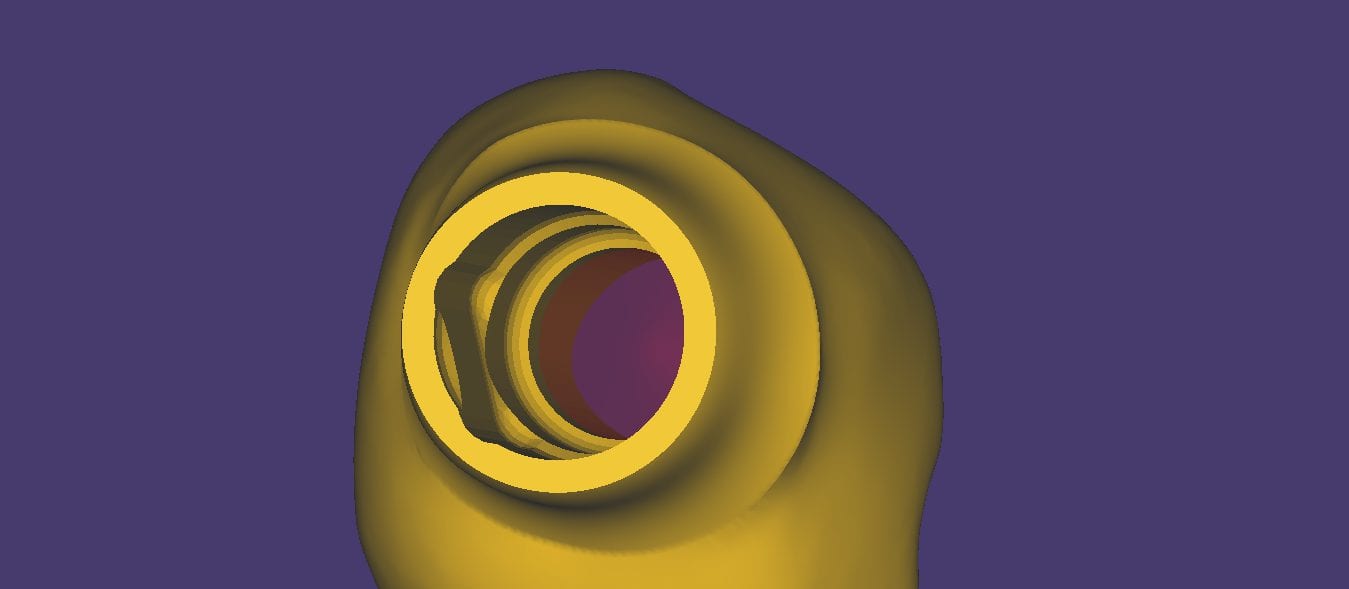

August 15, 2019In this article, we feature an upper left lateral crown that needed to be replaced due to recurrent decay. While the patient was getting numb, we defined the job description […]